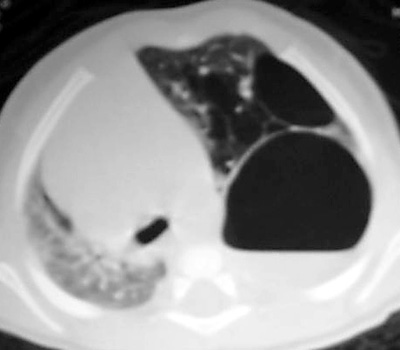

Chest CT on the same patient confirms a Type I CCAM with a large dominant cyst

surrounded by multiple smaller cysts